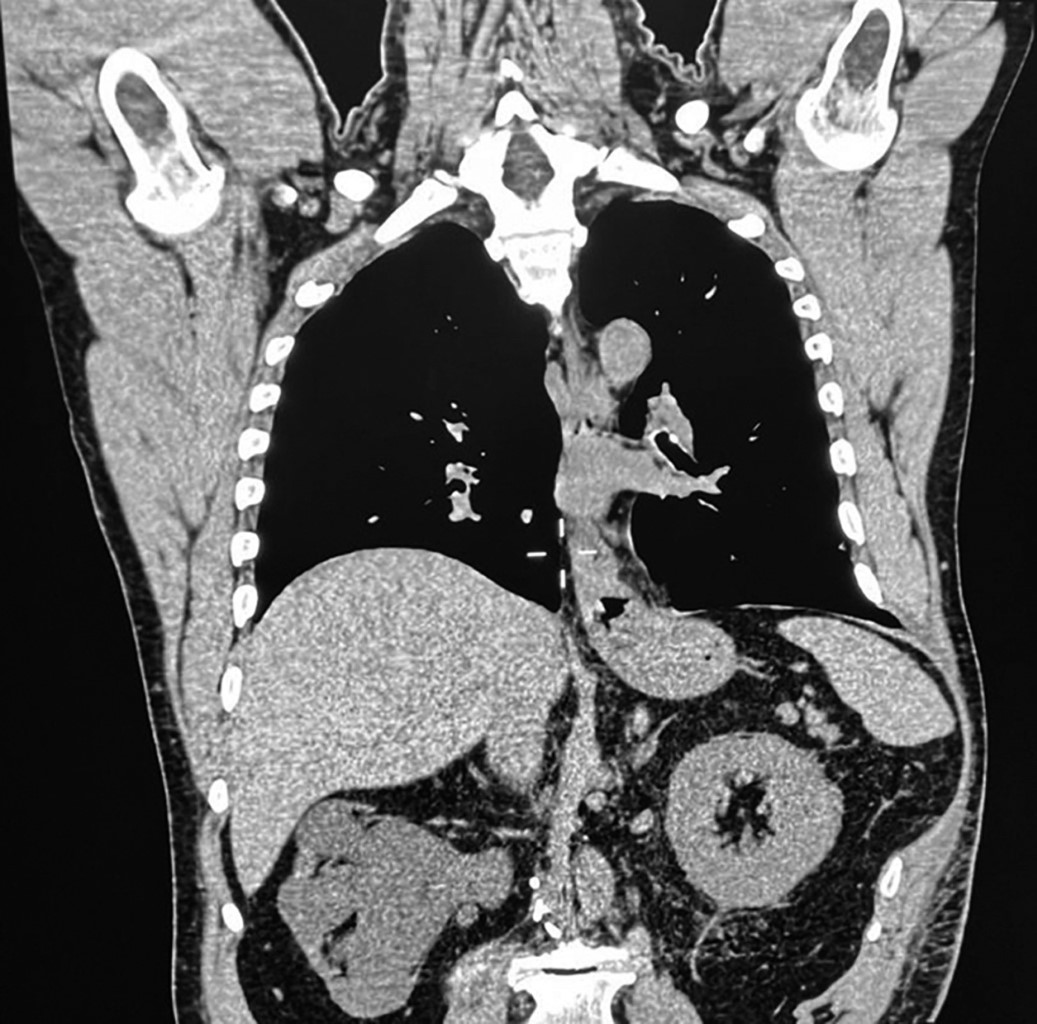

Hombre de 59 años con miocardiopatía dilatada (FEVI 59%, > 8 METS) y fracturas costales izquierdas tratadas conservadoramente en 2020. En 2024 consultó por aumento de volumen en la región intercostal izquierda al realizar esfuerzos físicos. La exploración evidenció un defecto reducible entre la novena y décima costillas izquierdas, y la tomografía confirmó la protrusión esplénica, diagnosticándose HIA (Figura 1).

Figura 1